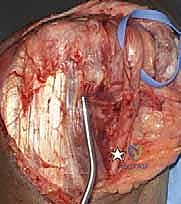

2. الشق الجراحي وحماية الأعصاب

يقوم الدكتور هطيف بعمل شق طولي خلف الكوع. الخطوة الأكثر أهمية هنا هي تحديد العصب الزندي (Ulnar Nerve) وعزله وحمايته بعناية فائقة باستخدام تقنيات الجراحة الميكروسكوبية الدقيقة لتجنب أي تلف قد يؤدي إلى ضعف في اليد.

3. إزالة العظام المحطمة وتحضير القناة العظمية

بمجرد الوصول إلى المفصل، يتم تقييم حجم الدمار. تُزال الشظايا العظمية المفتتة التي لا يمكن إنقاذها. بعد ذلك، يتم تحضير القناة الداخلية لعظم العضد (من الأعلى) وعظم الزند (من الأسفل) باستخدام أدوات قياس دقيقة جداً لضمان تطابق المفصل الصناعي مع تشريح المريض.